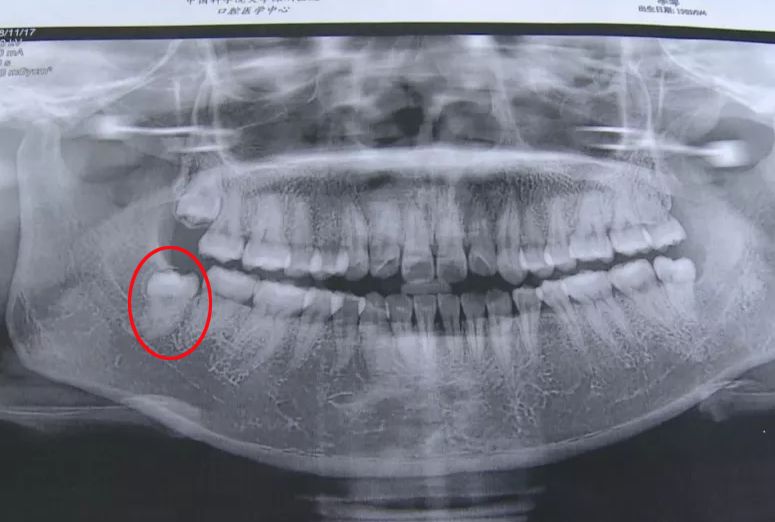

· 智齿所处的位置不同,其形态、结构也各有差异,一些患者的智齿结构极为复杂,拔除的难度十分之高,消耗的药品也有所增加,同时也十分考验医生的技术水平,在这种情况下,拔智齿的总费用就会更高一些。

▲阻生智齿